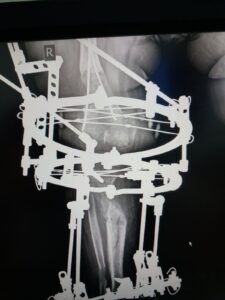

You can see the results of the treatment on the video. This was on January 2nd last year. When we looked and saw that the lengthened bones had grown properly and then we took off Ilizarov’s apparatus. It was necessary to wear the plaster for a certain time, so that the patient could use her leg without any fear. Also, to start walking in the period from when we removed the device until this examination. In the future, she should do exercise for the knees, ankle, and to strengthen her muscles.

The right doctor was found in the Atlas Hospital in Belgrade. Dad Nusret showed us a picture where you can see how big the problem was with Elma’s legs. They were in the shape of the letter O, and in the case of the left, the deformity was greater because the bone in the axis was completely inverted. After the operation and wearing the apparatus they are corrected now and parent’s happiness is endless. Every inch was important to them.